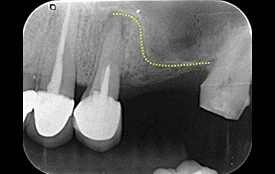

7. 上顎竇增高術

上顎竇位於上顎後牙區的正上方,是副鼻竇的一種,基本上是個充滿氣體的腔室,牙齒拔除後,上顎竇可能往下延伸到無牙區,造成缺牙區齒槽骨的不足。

本院利用專利器械將上顎竇膜提高並降低黏膜穿孔破裂的機率及避免術後感染(有時會合併骨粉)的使用,以利人工植體植入。

↑ 治療後:微創補骨增高鼻竇,不腫脹